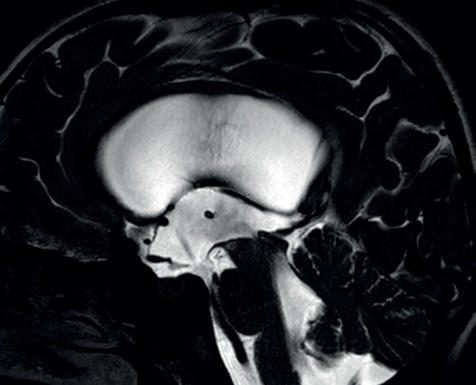

V naší kazuistice hraje ústřední roli patnáctiletá dívka, která byla sledována dětskou neuroložkou pro měsíce trvající silné bolesti hlavy. Tyto byly lokalizovány do oboustranných spánkových oblastí bez návaznosti na specifické činnosti, polohu či jiné faktory. Bolesti byly přítomny denně, dívka často vynechávala ve škole, kde se i beztak její prospěch horšil kvůli poruše pozornosti a paměti. Ošetřující neuroložka indikovala magnetickou rezonanci (MR) mozku, kde byla nalezena dilatace komorového systému (obr. 1). S tímto byla pacientka přijata do naší péče. V anamnéze nebyly vystopovány žádné rizikové faktory pro vznik hydrocefalu – perinatální anamnéza byla negativní, pacientka neprodělala žádný neuroinfekt či úraz hlavy. Na MR mozku byla viditelná výrazná dilatace komorového systému, zejména supratentoriálně, nicméně ani IV. komora nebyla fyziologické šíře. Dále bylo nápadné zúžení vtokové části aquaeductus mesencephali s velmi výrazným tokovým artefaktem na PSIF, tedy sekvenci určené k detekci toku likvoru (obr. 2), obraz zúžení mokovodu s hyperdynamickým tokem likvoru. To podporoval i výrazný bowing III. komory, tedy vyboulení III. komory a vyhlazování jejích výklenků, turecké sedlo však nebylo zvětšeno ani nikterak destruováno (obr. 3). Po příjmu pacientky byla provedena optická koherentní tomografie (OCT) zrakového nervu, která edém terče zrakového nervu neprokázala. Vzhledem k tomu, že se nejednalo o jasný obstrukční hydrocefalus, byla následně provedena lumbální punkce ke změření tlaku likvoru a odběru jeho vzorku k laboratorní analýze. Tlak byl v normě – 17 cm H20, v laboratorních vyšetřeních odchylka též nebyla nalezena. To znamená, že na MR mozku jsou jasné známky hydrocefalu, ale jak nález na očním pozadí, tak i lumbální punkce ukazují na normální tlak mozkomíšního moku. Vzhledem ke zmíněnému výraznému tokovému artefaktu likvoru přes aquaeductus mesencephali jsme se zaměřili na tento fenomén. Provedli jsme MR mozku metodou fázového kontrastu (Phase‑Contrast MRI, PC‑MRI), která umožňuje tokové parametry likvoru kvantifikovat. Opravdu se potvrdilo, že tok likvoru je hyperdynamický, maximální systolická rychlost byla 11,7 cm/s (obr. 4). Byla tedy vyslovena hypotéza, že se jedná o stenózu mokovodu a pacientce, a vzhledem k věku samozřejmě i rodině, byla navržena endoskopická stomie III. komory (ETV). Vzhledem k absenci mechanické obstrukce mokovodu při současně vysokých systolických rychlostech průtoku likvoru přes mokovod byla vyslovena hypotéza, že se jedná o funkční stenózu mokovodu. S přihlédnutím k věku pacientky byly ona i její rodina seznámeny s možností miniinvazivního výkonu ve smyslu endoskopické stomie III. komory (ETV). Rodina byla však k operaci rezervovaná, proto jsme nabídli tehdy novou diagnostickou metodu – miniinvazivní přímé měření intrakraniálního tlaku (ICP) čidlem s telemetrickým přenosem naměřených hodnot (Raumedic Neurovent‑P‑telâ). Hlavní výhodou této metody je možnost kontinuálního měření ICP i v domácím prostředí až po dobu 90 dnů. Implantace čidla byla provedena bez komplikace a pacientka byla edukována o způsobu monitorace ICP, zejména vedení deníku činností a bolestí hlavy. Po třítýdenním měření byla data analyzována a porovnána s deníkem. Byl nalezen jasný korelát mezi silnou cefaleou a hroty ICP až k hodnotám 30 mm Hg. Zvláště nápadné byly křivky během noci, kdy krátce po elevaci ICP byla pacientka bolestmi hlavy opakovaně vzbuzena. Po předložení výsledků této metody pacientka i rodina souhlasily s provedením ETV. Zákrok byl proveden bez komplikace, průchodnost stomie byla verifikována pooperačním vyšetřením pomocí MR mozku (obr. 5). Pooperačně se však symptomy pouze zmírnily a po pěti týdnech nastala kompletní recidiva obtíží. Byla vyslovena suspekce na okluzi stomie, nicméně kontrolní MR mozku toto nepotvrdila. Další postup mohl mít dva scénáře. První by znamenal připustit, že pacientčiny nespecifické symptomy nebyly dány porušenou likvorodynamikou a naše rozvaha byla chybná. Druhý by znamenal setrvání v našem předpokladu, že obtíže jsou spojeny s likvorodynamickými poměry, nicméně ETV nepostačovala k odvedení dostatečného objemu likvoru při jeho pulzatilním toku. Jedinou další léčebnou metodou by v tom případě bylo zavedení ventrikuloperitoneálního (VP) shuntu. Což je však další invazivní výkon, proto jsme uvažovali o další diagnostické metodě – lumbální drenáži. Jedná se ve své podstatě o simulaci zavedeného shuntu dočasnou drenáží likvoru ze spinálního subarachnoidálního prostoru. Po domluvě s pacientkou a rodinou byla lumbální drenáž zavedena a ponechána tři dny s celkovým objemem odvedeného likvoru 500 ml. Po celou dobu drenáže byla pacientka zcela bez bolestí hlavy. Test byl tedy pozitivní. Po vytažení drenáže se bolesti vrátily do dvou dnů. Nyní jsme s větší jistotou mohli indikovat zavedení VP shuntu. Protože jsme předpokládali, že nastavení ventilu shuntu nebude u takto komplexního typu hydrocefalu jednoduché, zavedli jsme typ ventilu, který umožní regulaci tlaku separátně pro horizontální a vertikální polohu těla – Miethke proGAVâ 2.0 s iniciálním nastavením 10 cm H2O a m.Blueâ s nastavením 25 cm H2O (obr. 6). Operace proběhla bez komplikace a pacientka byla propuštěna do domácího ošetřování s tím, že případné změny nastavení ventilu budou provedeny v rámci ambulantních kontrol. Při první kontrole pacientka udávala přetrvávající bolesti hlavy, proto bylo nastavení ventilu proGAVâ 2.0 pro horizontální polohu sníženo na 5 cm H2O. Při další kontrole za dva týdny pacientka popisovala kompletní vymizení původních příznaků vleže. Popisovala však symptomy předrénování, tedy výraznou cefaleu při vertikalizaci s rychlou úlevou v horizontální poloze. Proto bylo nastavení antigravitační jednotky m.Blueâ postupně zvýšeno až na maximum, tedy 40 cm H2O. Na tomto nastavení byla nalezena rovnováha mezi potřebou nízkoodporové drenáže likvoru vleže a zamezení předrénování sifonovým mechanismem vstoje. Pacientka je nyní sledována po operaci jeden rok, je zcela bez bolestí hlavy.